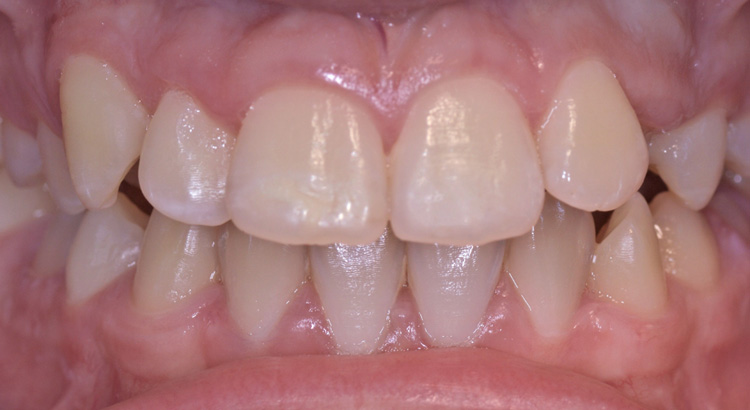

Odontoiatria Estetica

Questo giovane paziente vuole migliorare l’estetica del suo sorriso preservando però il suo dente da eventuali interventi sullo smalto. In particolare vuole cambiare la forma dell’incisivo centrale e diminuire gli spazietti neri tra gli incisivi laterali e i canini. Grazie all’utilizzo di materiali compositi ad alta esteticità è stato possibile ripristinare la corretta estetica del sorriso. Paziente contentissimo del suo nuovo sorriso.